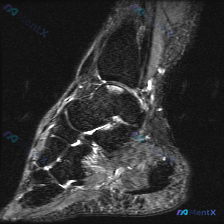

看到这张踝关节MRI,整理一下读片思路和分析,分享给大家一起讨论。 病例影像基本信息 这是一张踝关节矢状位T2加权脂肪抑制MRI影像,我们来系统梳理一下所见: 核心影像学发现 1. 跟腱区域(重点异常):跟腱止点及其近侧的肌腱内部可见明显条片状高信号,提示水肿、炎症或者肌腱内部结构改变;同时跟腱前方...